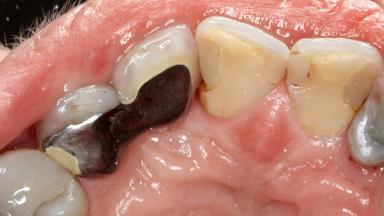

Despite anti-infective surgical treatment, some patients may experience recurrent infection and progressive bone loss requiring additional treatment. This case describes a conservative approach using an implant retrieval tool without the need for excessive bone removal or use of a trephine.

A 65-year-old female patient was referred to the periodontist for assessment and management of infection associated with an implant at site 12. The general dentist had noted suppuration on probing during examination.